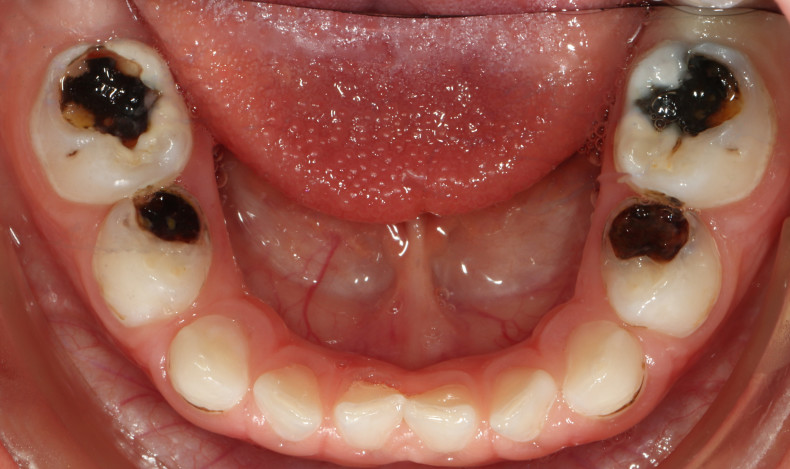

Silver Diamina Flouride atau biasa disingkat SDF adalah salah satu treatment untuk menghentikan karies gigi pada anak.

Kandungan fluoride dalam cairan SDF bertujuan untuk meningkatkan kekuatan gigi dengan mempromosikan remineralisasi emailatau lapisan luar gigi yang keras. Sementara itu, kandungan perak di dalamnya dapat membunuh bakteri yang menyebabkan karies, alias gigi berlubang.

- Tidak hanya mencegah karies menyebar atau bertambah besar, Silver Diamine Fluoride juga dapat mencegah munculnya gigi berlubang di masa mendatang.